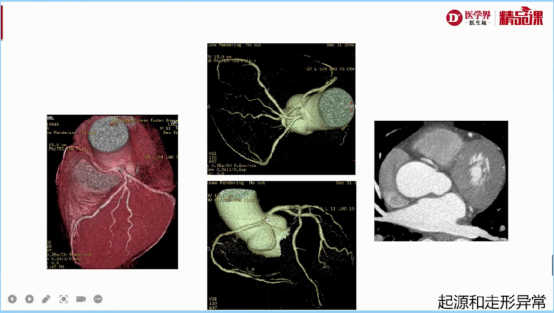

1.容积重建(VR):冠脉立体结构,只看冠脉起源、走形,不看狭窄

图3:容积重建冠脉走形异常举例

图4:容积重建冠脉出口异常举例